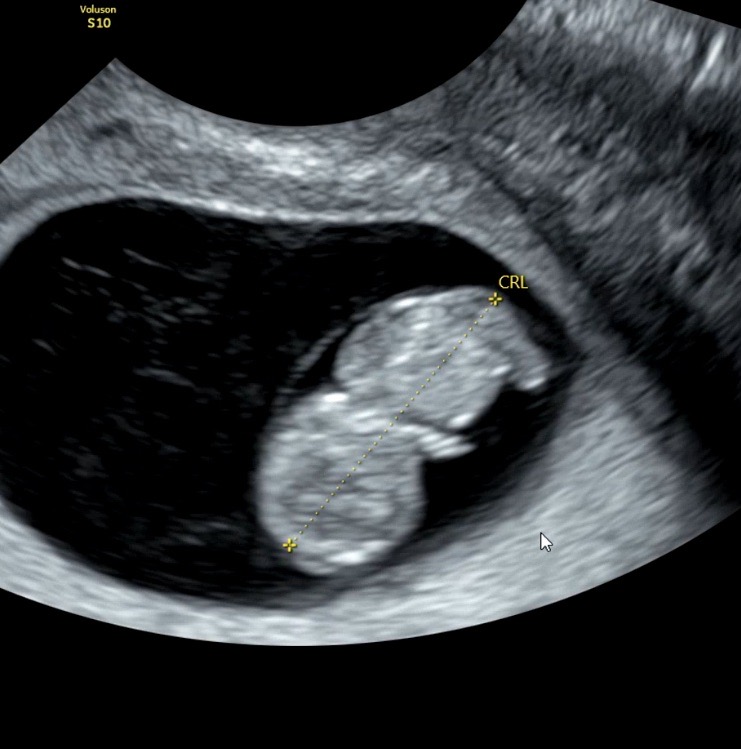

8주차 아기 성별각도법

다음주가 12주차인데 혹시 8주차 사진으로도 성별각도법 알수있나요? 너무 너무 궁금하네요

8주차로는 절대알수 없구요 ㅎㅎㅎ 12주차되면 각도법으로 유추가능해요!^_^

ㅎㅎ각도법은 모르겠고 2등신 넘 귀엽네요 ㅋㅋ 초음파 화질 좋은거 부러워요